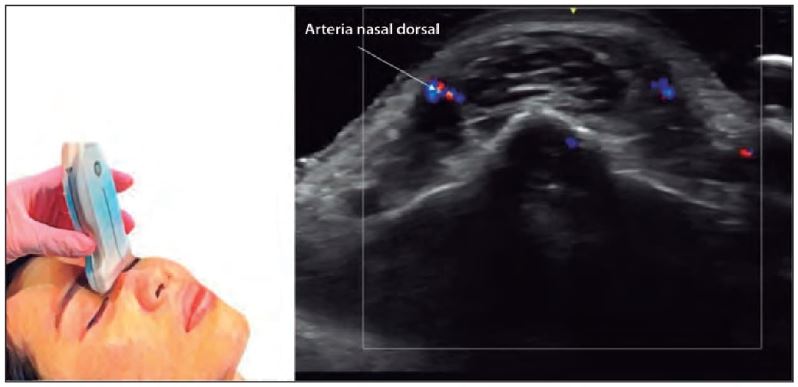

Un conocimiento profundo de la anatomía nasal es indispensable para realizar procedimientos seguros. La ecografía permite visualizar:

- Estructuras vasculares: Arterias como la angular, nasal lateral y ramas de la arteria oftálmica.

- Modos B y Doppler en color: Para evaluar estructuras anatómicas y flujo vascular.